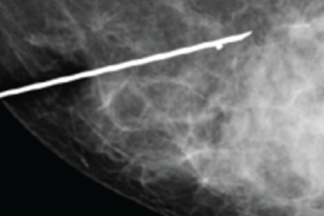

El marcaje con guía ultrasonográfica, previo a la obtención de la biopsia, es uno de los procedimientos más utilizados para el diagnóstico de lesiones malignas o premalignas.